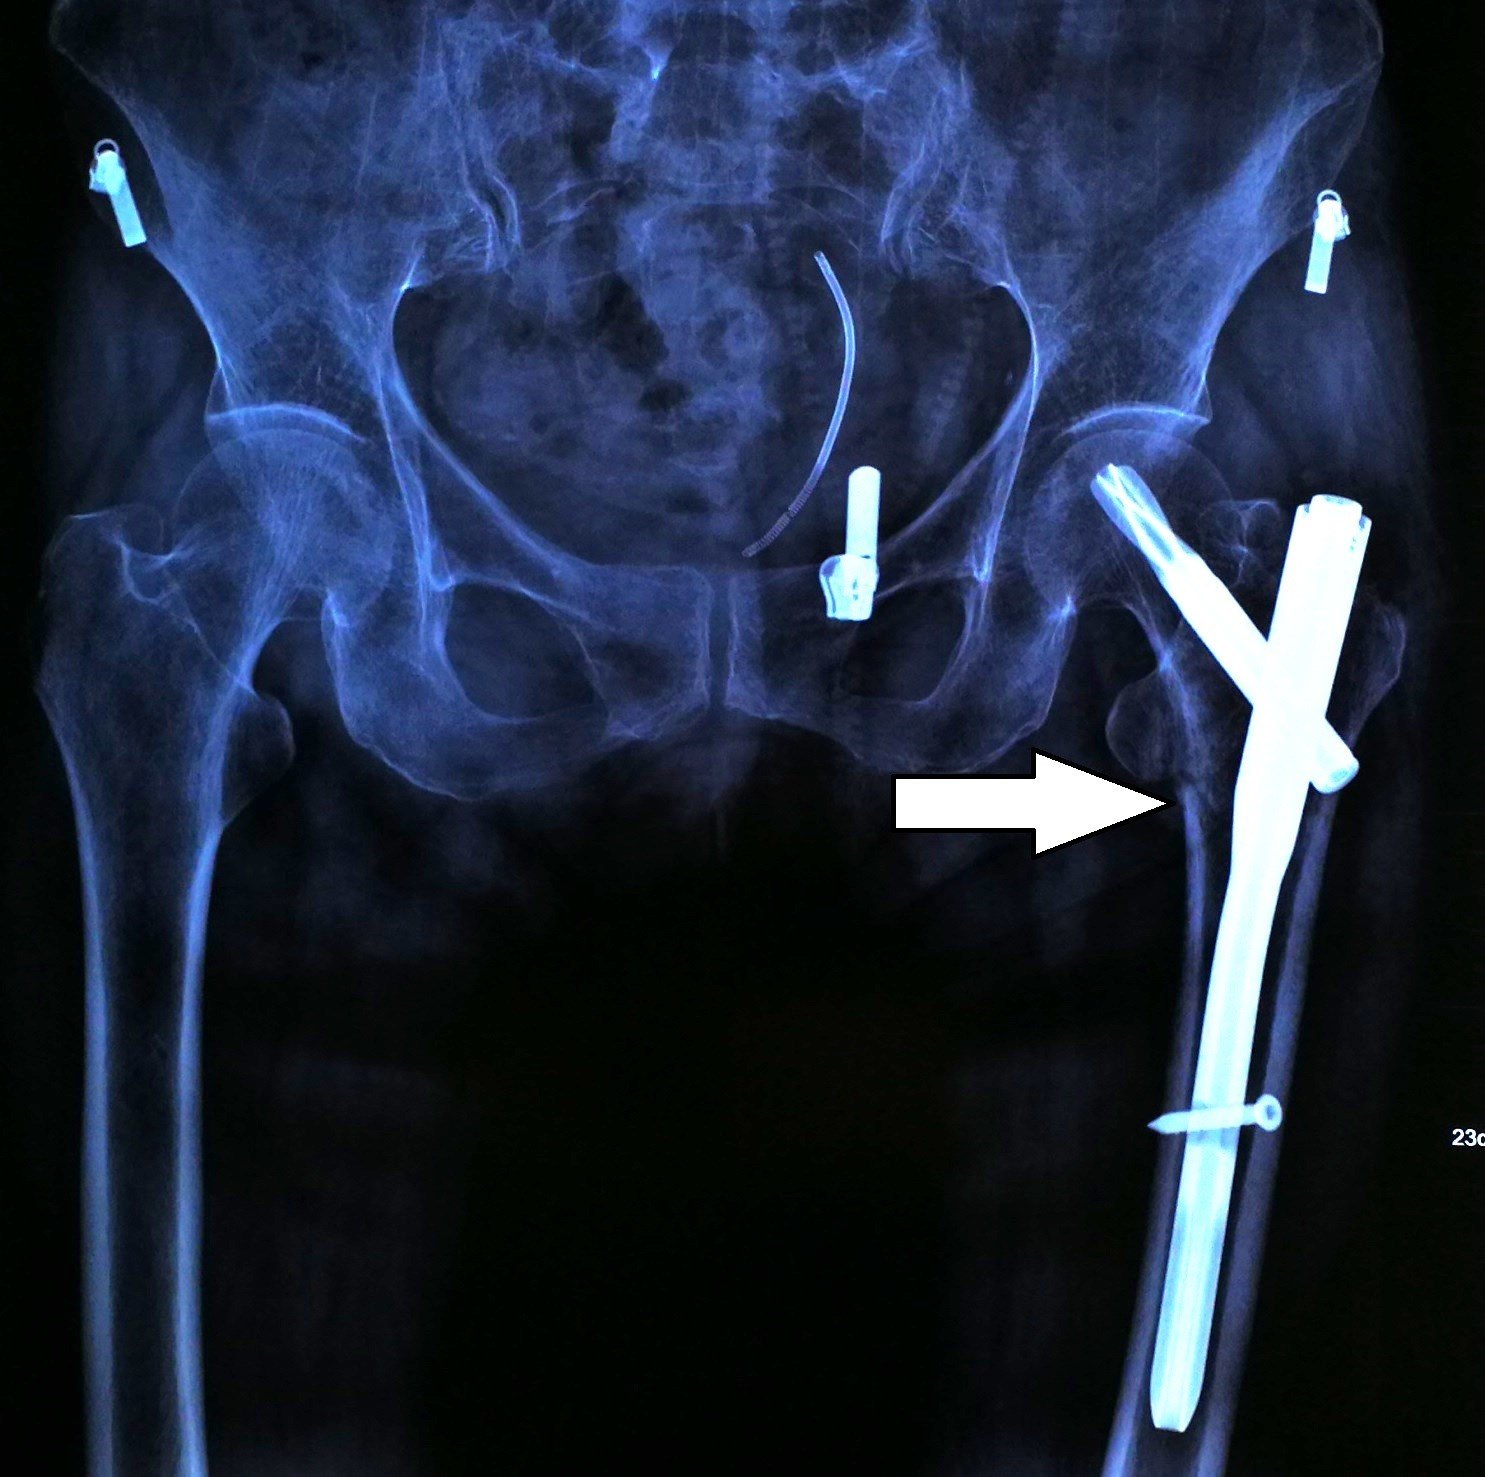

髋关节骨质疏松骨折治疗的完美演绎